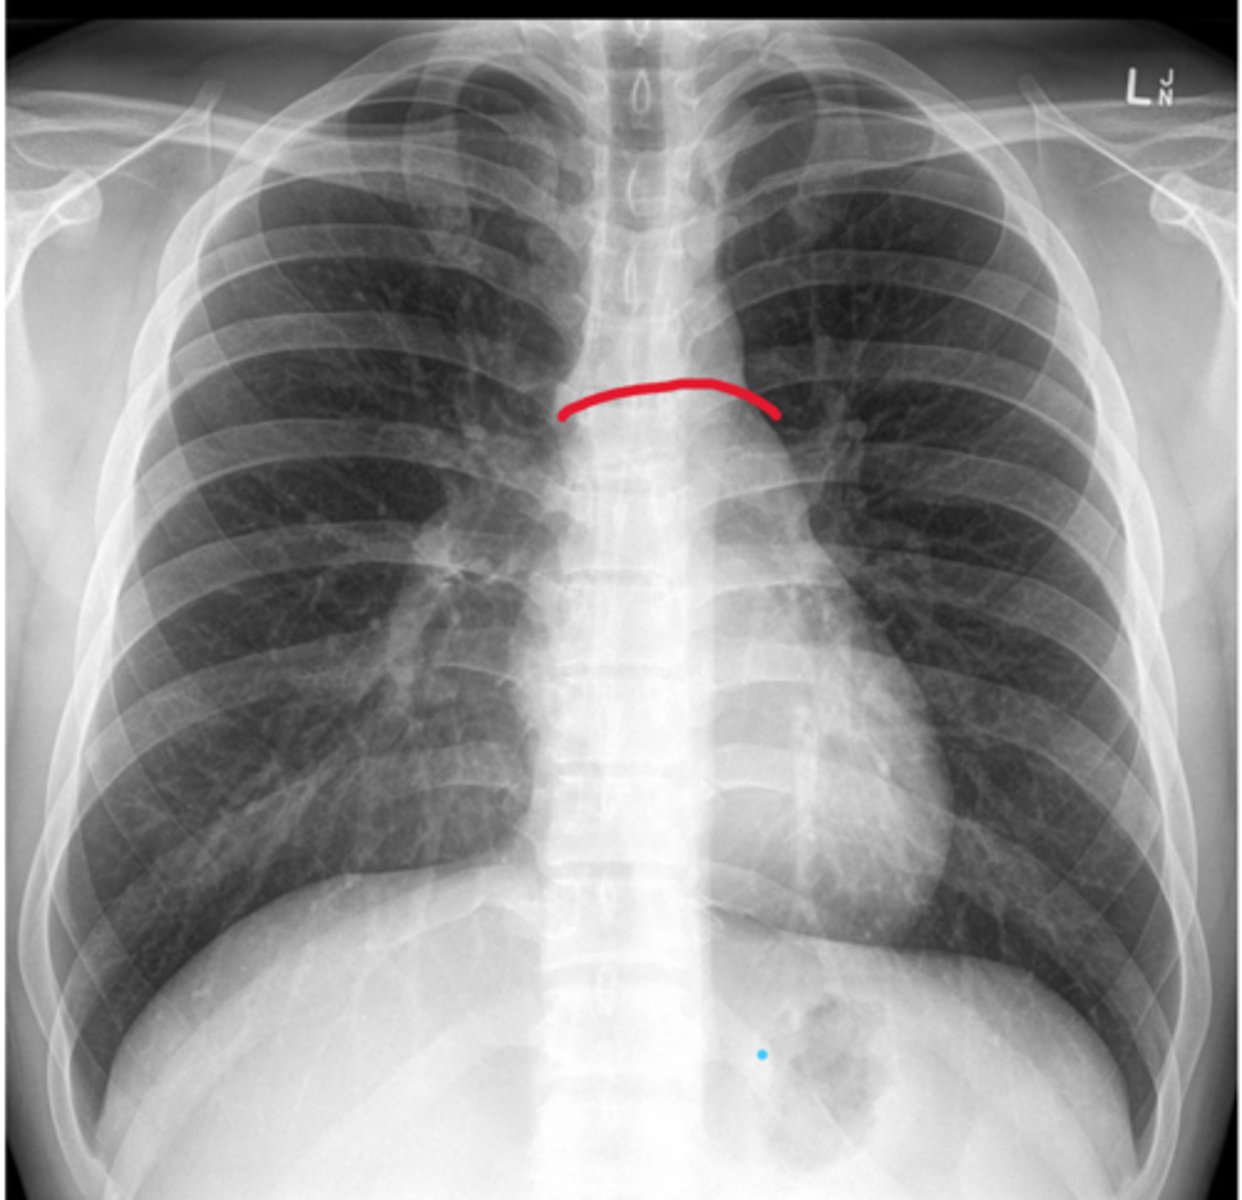

Right border of the heart

Boundary; X-ray, medial edge

L border of the heart

Boundary, X-ray, lateral edge, apex points this way

Inferior border of the heart

Boundary; X-ray, bottom edge

Superior border of the heart

Boundary; X-ray, top edge

Coronary sulcus

Depression, goes from Right auricle to Left auricle, probe lays in